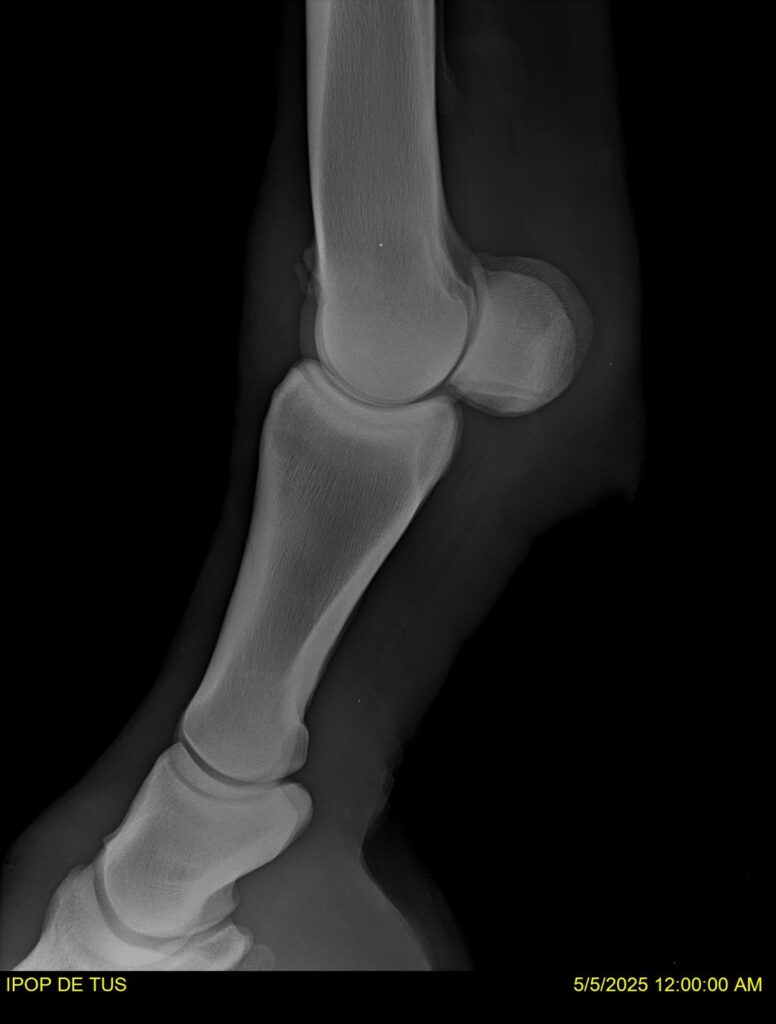

IPOP DE TUS, selle français, hongre, prendra 8 ans en 2026. LIFESTYLE x EROTICBLUS MONTOIS. Sans faute sur 125 et 130. Gentil cheval, respectueux avec des moyens et de la force. Transport OK, maréchalerie OK (pieds nus), santé RAS, Bilan clichés radios + clinique OK.

RADIOS ET CLINIQUE